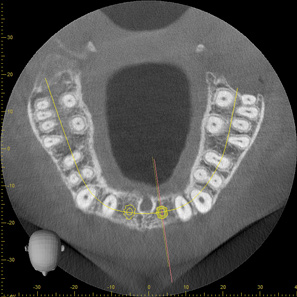

Fig 2. CBCT images show axial (Fig 2) and cross-sectional (Fig 3) views, and 3D reconstruction view (Fig 4) with virtually planned implant Nos. 8 and 9.

Figure 2

Fig 3. CBCT images show axial (Fig 2) and cross-sectional (Fig 3) views, and 3D reconstruction view (Fig 4) with virtually planned implant Nos. 8 and 9.

Figure 3

Fig 4. CBCT images show axial (Fig 2) and cross-sectional (Fig 3) views, and 3D reconstruction view (Fig 4) with virtually planned implant Nos. 8 and 9.

Figure 4

For dental implant-based treatment, the planning phase begins with collection of basic data sets; this is digital touchpoint 1. It includes: (1) a cone-beam CT (CBCT) to view edentulous areas or failing tooth structure, bone, and anatomic landmarks under the soft tissue (Figure 2 through Figure 4); and (2) an intraoral optical scan (IOS) or a scanned model or impression to record the soft tissue and tooth anatomy (Figure 5). The superimposition of the digital imaging and communications in medicine (DICOM) files from the CBCT and the standard tessellation language (STL) files from the IOS allows visualization of how bone, dental structures, and soft tissues relate. Both digital data points are key to implant selection and determining the surrounding bone-grafting needs. An initial treatment plan includes determining the desired implant manufacturer/implant design, size, and positions; these decisions remain the responsibility of the dentist (restoring and surgical team members) and not the technician or planning team.